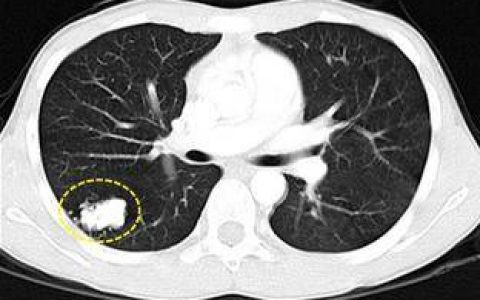

• Radiology:CT检查可降低肺结节的活检和手术率。

一项发表在《放射学》杂志上的新研究称,通过每年低剂量计算机断层扫描(CT)可以避免非实性肺结节活检或手术。 非实性结节(NSNs)通常是肺部无症状的生长。此名称来源于正常肺组织内可见的结节CT图像。随着医疗保险和…